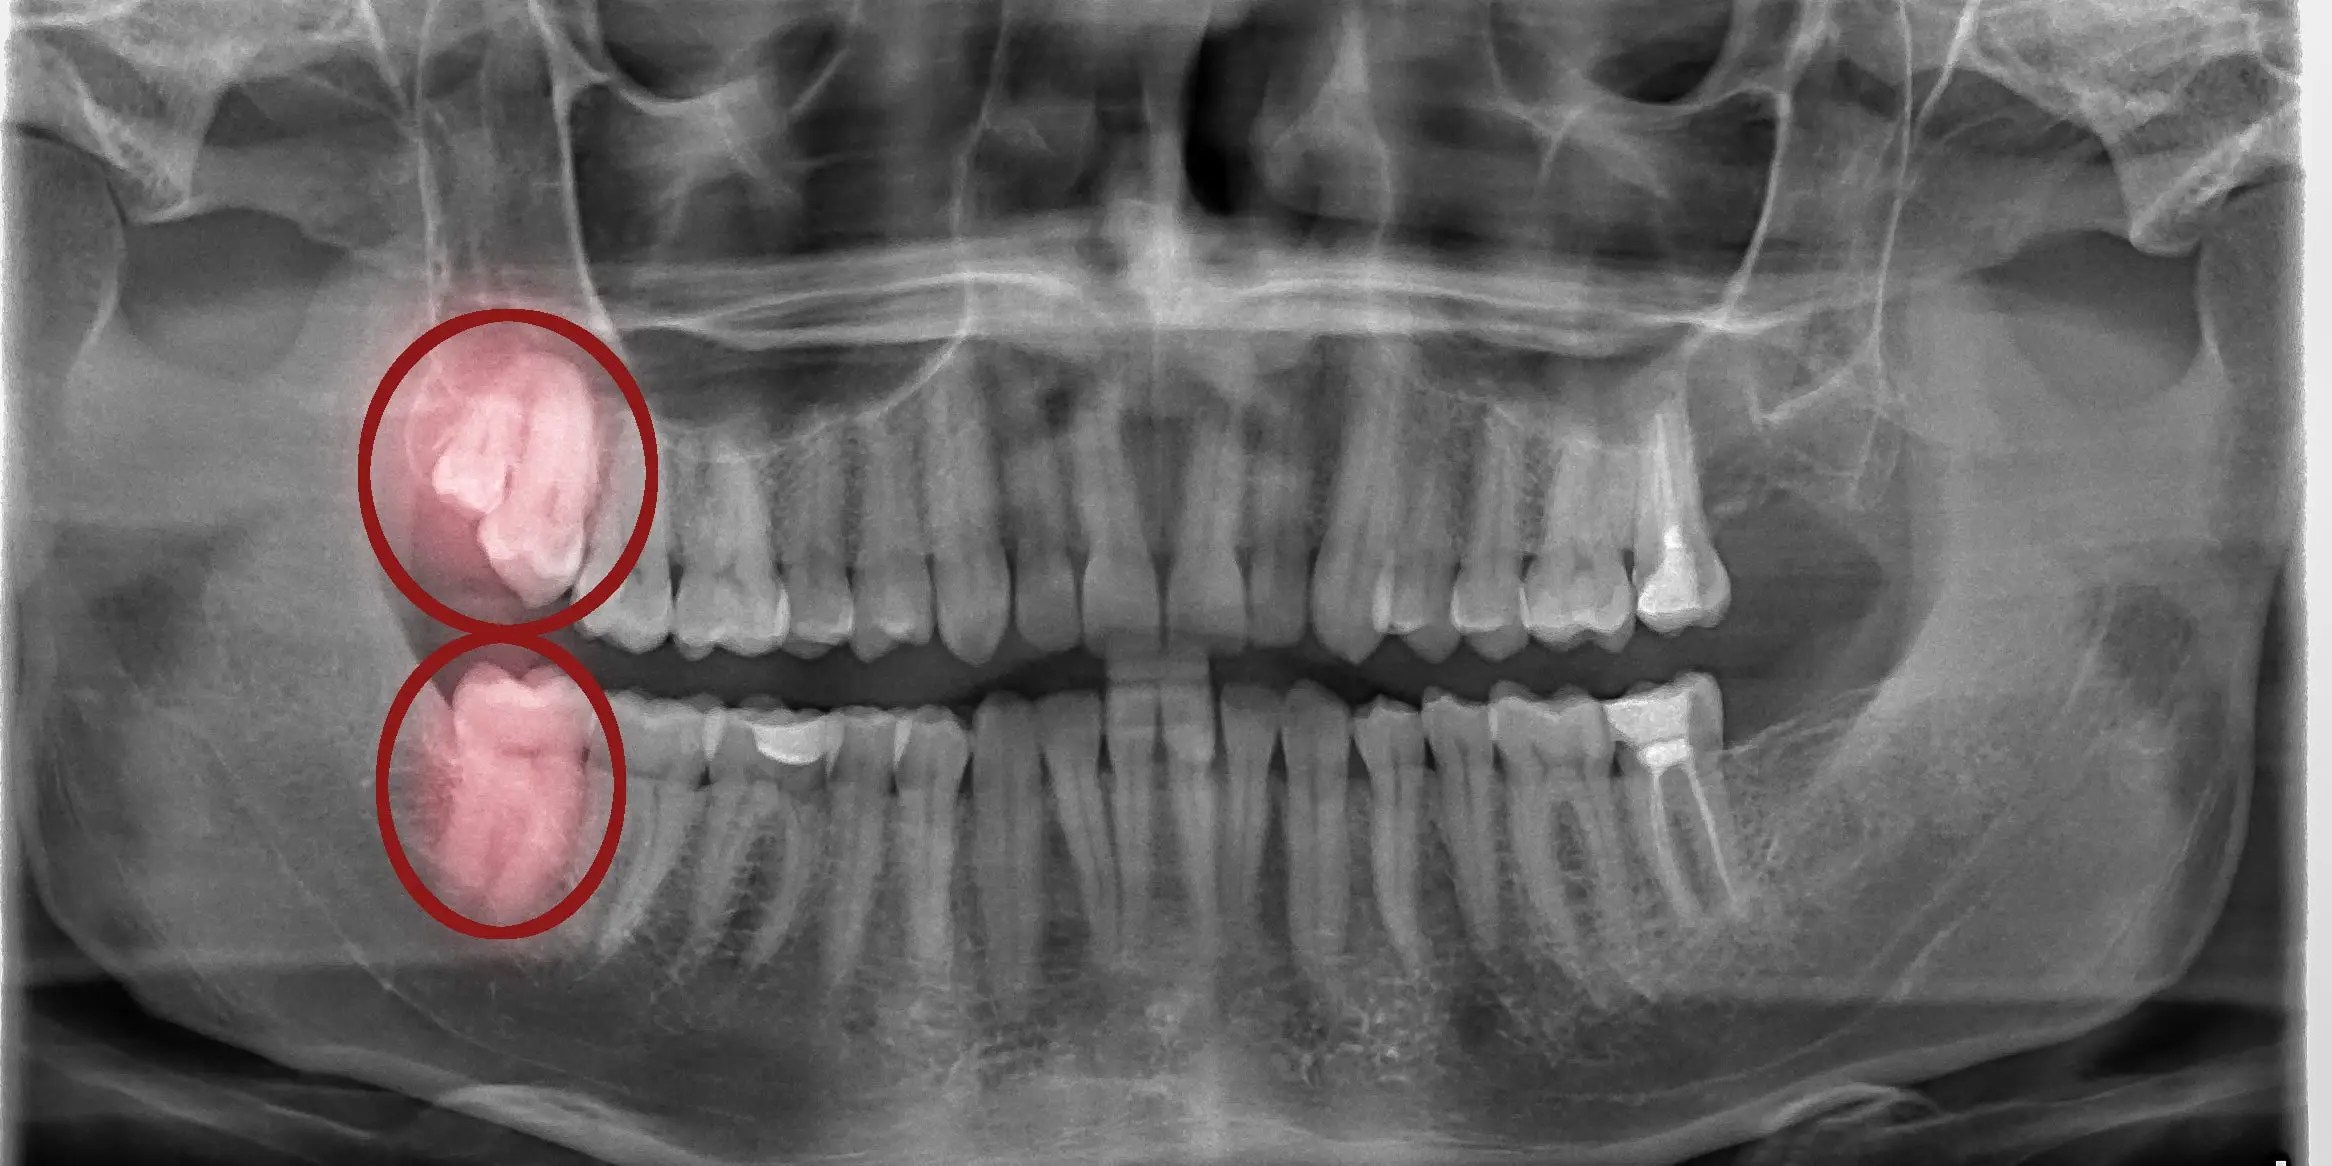

impacted wisdom teeth symptoms treatment dentique dental clinic